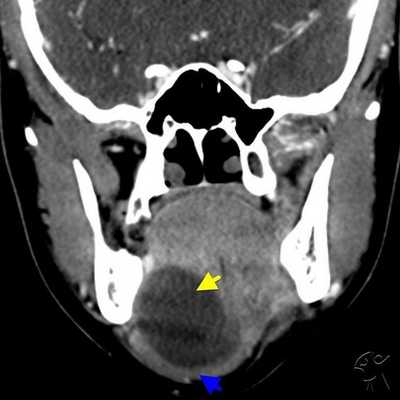

Для выявления болезней слюнных желез (сиалоаденит, синдром Шегрена, закупорка протоков камнями) применяются лучевые методы - КТ, МРТ, УЗИ. Специфичность компьютерной томографии при нозологических формах около 100%, достоверность - 98%. Показатели высокие для достоверной верификации патологии околоушных, подчелюстных желез. Ограничивает повсеместное применение метода радиационное облучение. Разовая обследование не приносит вреда, но не рекомендуется делать сканирование часто (за исключением верификации новообразований).

КТ-признаки слюннокаменной болезни

Отечность, увеличение околоушной и поднижнечелюстной областей, не проходящие после приема фармацевтических препаратов - показание к лучевой диагностике. Симптомы обуславливает не только сиалоаденит. Слюннокаменная закупорка (сиалолитиаз) определяется после КТ-сиалографии по следующим признакам:

- Увеличение размеров поврежденного органа;

- Сохранение однородности структуры;

- Расширение протока.

Дополнительно врач лучевой диагностики укажет плотность ткани. Признак является дифференциальным маркером определения эффективности проводимой терапии с целью отслеживания динамики на повторных томограммах.

Тонкосрезовая СКТ головы и слюнных желез с трехмерным моделированием (3D) создает пространственную структуру, с помощью которой врачи устанавливают внутрипротоковое расположение камня.

Применение обследования помогает обнаружить аденокарциному слюнной железы - злокачественную опухоль, склонную к быстрому прогрессированию, прорастанию близлежащих тканей. Онкология чаще обнаруживается случайно, так как не имеет специфических внешних признаков.